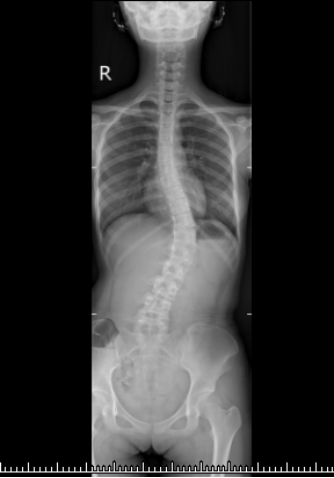

甜甜术前脊柱DR影像

近日,甜甜的父母在朋友介绍下来到西南医科大学附属中医医院骨伤科脊柱•肿瘤一组求诊。陈光友主任中医师收治住院后发现,甜甜脊柱侧弯以胸腰弯为主,角度已达47°,椎体旋转3度,且骨骼发育还没完全停止,保守治疗疗效不佳,无法阻止病情进展,甚至还会加重。若想矫正畸形,恢复正常身形,必须手术治疗。

细心的妈妈发现了问题:甜甜的变化不仅仅是身高,从身后望去,她的身形呈“S”型,骨盆两侧一高一低。这下,妈妈慌了神,立即带着甜甜到医院就诊,最终被确诊为“青少年特发性脊柱侧弯”。